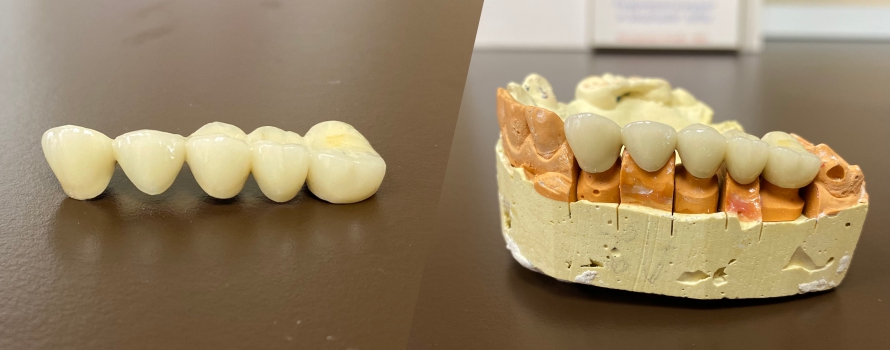

Разновидности зубных коронок и их особенности